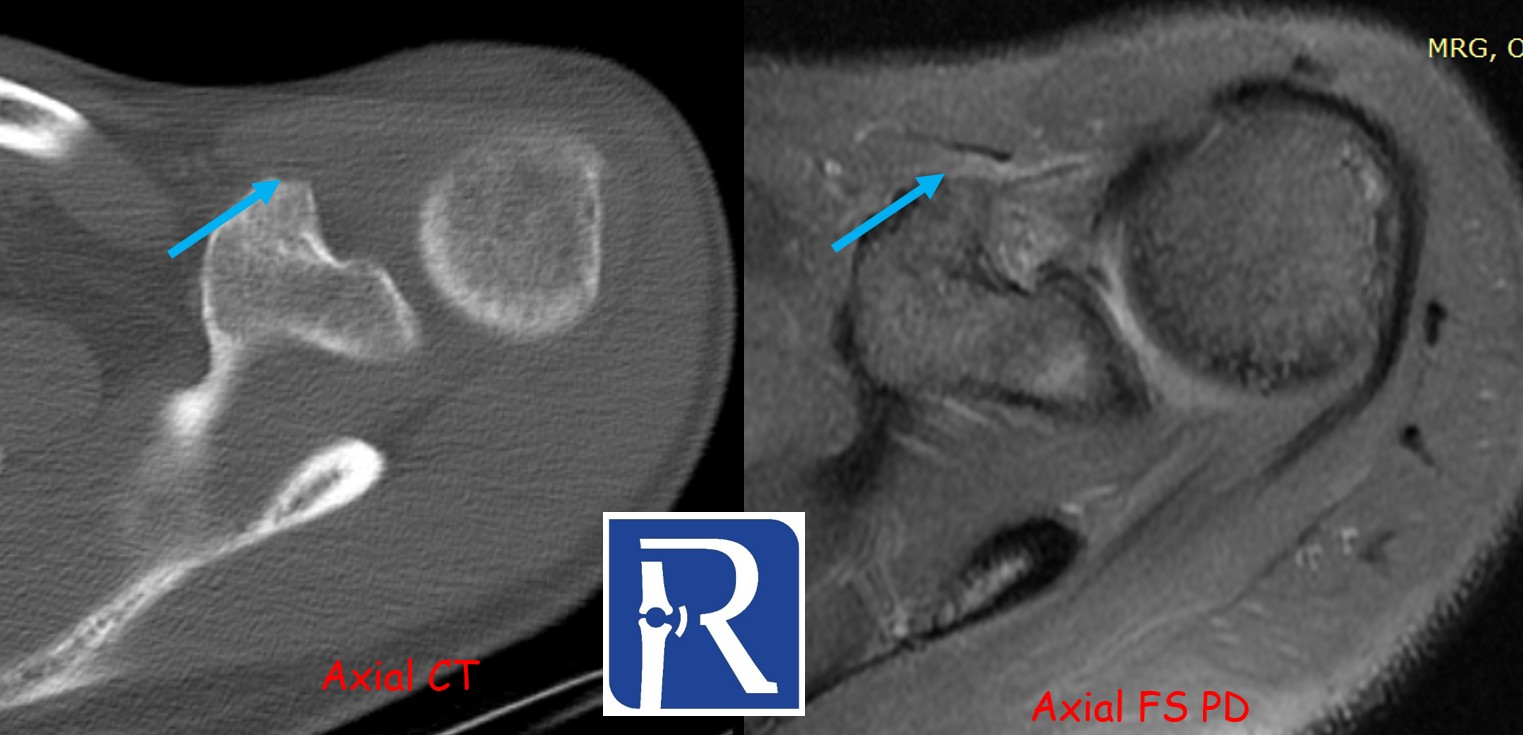

CT Findings:

CT demonstrates a bony defect at the coracoid process (blue arrows) and shows that the resected bone fragment has been fixed to the inferior glenoid defect with two anchors (white arrows). These findings are consistent with a Latarjet procedure.

A radiolucent anchor is also identified at the superior glenoid, corresponding to the site of the labral repair (red arrows).